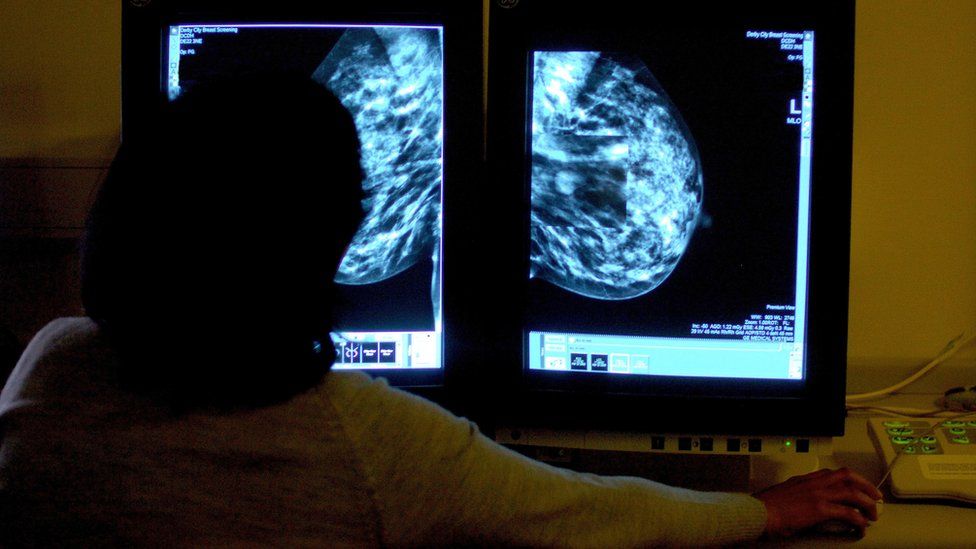

Key cancer cells waiting time target set to be missed in England

The NHS is readied to miss an essential cancer cells therapy target laid out in the Covid recovery strategy, the nationwide cancer cells director for England has actually stated.

The NHS had actually dedicated to cutting the stockpile of people waiting greater than 2 months to be detected and also begin cancer treatment to pre-pandemic levels.